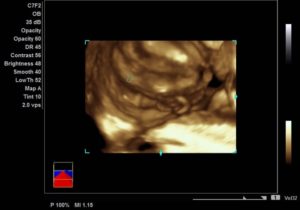

При внимательном изучении изображения на мониторе можно увидеть характерные признаки:

• для девочек: визуализируются 2 или 4 прямые тонкие линии, которые в дальнейшем формируют малые и большие половые губы;

• для мальчиков: в поперечном положении плода определяются зачатки пениса и мошонки.

Ближе к 16 неделе развития малыша половые признаки становятся более определенными. Наверняка можно узнать пол ребенка на УЗИ на сроке 20-24 недели, при условии, что плод занимает правильное положение в полости матки. Но следует учесть некоторые физиологические особенности, которые могут искажать данные — толщина стенки матки, количество околоплодных вод. На этом сроке чаще всего выполняют 3D-УЗИ с фотографированием будущего малыша.

• В течение первых двух месяцев формируются яичники у девочек и яички у мальчиков. Начальная стадия развития еще не позволяет точно визуализировать половую принадлежность.

• У мальчиков на 11 неделе начинается выработка дигидротестостерона, отвечающего за формирование полового органа. Из небольшого бугорка начинает развиваться член, сращиваются половые складки и образуется мочеиспускательный канал. У девочек бугорок преобразуется в клитор, а половые складки — в половые губы. Достаточно опытный врач-диагност уже может делать выводы о половой принадлежности плода. Однако вероятность ошибки в данном определении очень высока.

• После 18 недели сформированы половые органы. В ходе ультразвукового обследования весьма доступно определение пола малыша. Если нет никаких препятствий, родители выходят из кабинета в твердой уверенности, какого цвета готовить приданое для младенца.